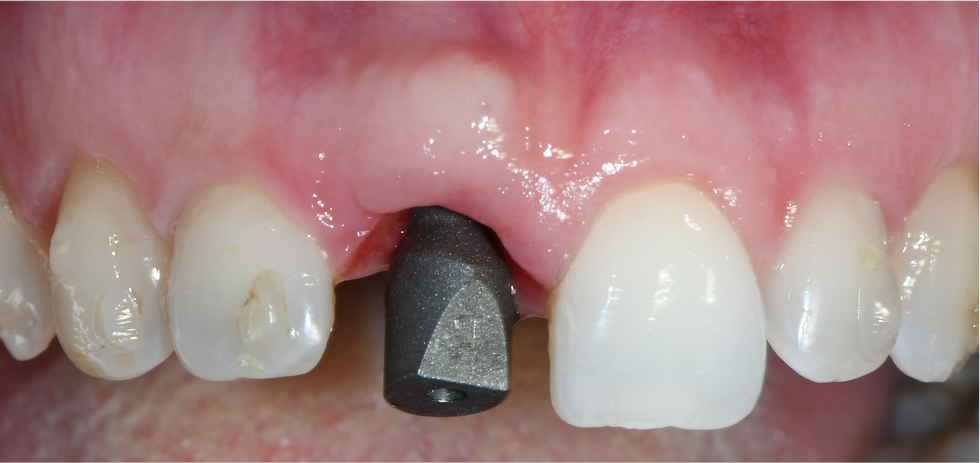

Traumatic fracture of element 1.1

Implant placed in the post-extraction socket